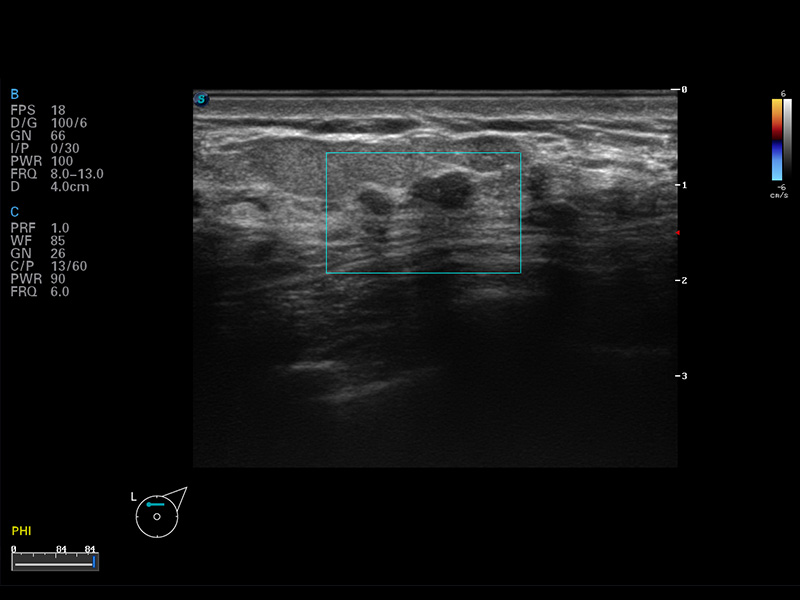

S8 EXP便携式彩色多普勒超声诊断仪是环球UG官网研发的高端全身应用型便携彩超。高通道的VIS平台融合可视化(Visual)、智能化(Intelligent)和人性化(Smart)的特点,配以环球UG官网自主研发生产的探头大家族,使您能够快速、准确的获得病人信息,提高工作效率的同时减轻疲劳。

成像技术

多波束形成器

μ-Scan微米成像

谐波成像

实时宽景成像

空间复合成像

3D/4D成像